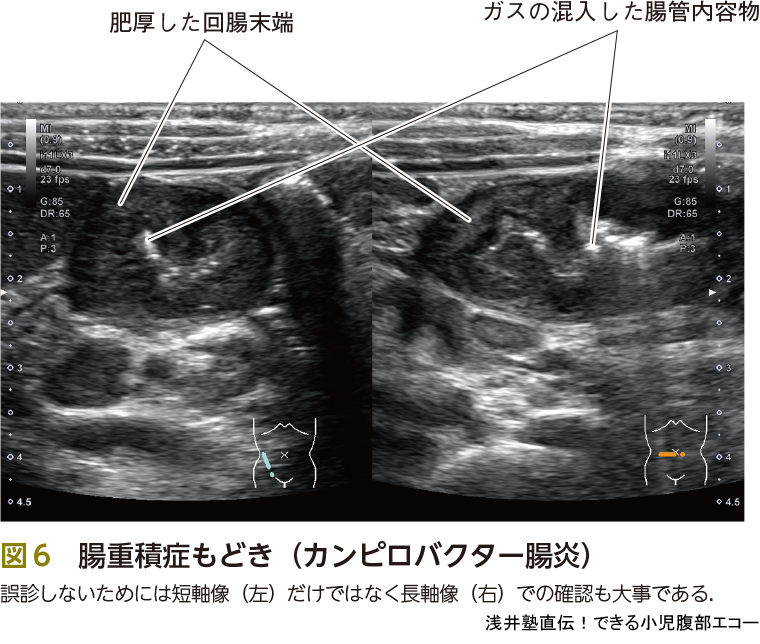

最後に紛らわしいもの,経過観察でいいもの(いわゆる,もどき)をピットフォールで記載いたしますので参照下さい(図6,7,ピットフォール②).

当直医は短軸像のみしか確認していませんでした.スキルアップしたら層構造の確認から短軸像のみでも診断可能ですが,基本的に長軸と短軸両方で確認する必要があります.なお,粘膜,粘膜下層が肥厚し低エコーとなっています.その内部にみえる高エコーが腸管の内容物にairが混入した所見になります.結果,この症例はカンピロバクター腸炎でした(図6).